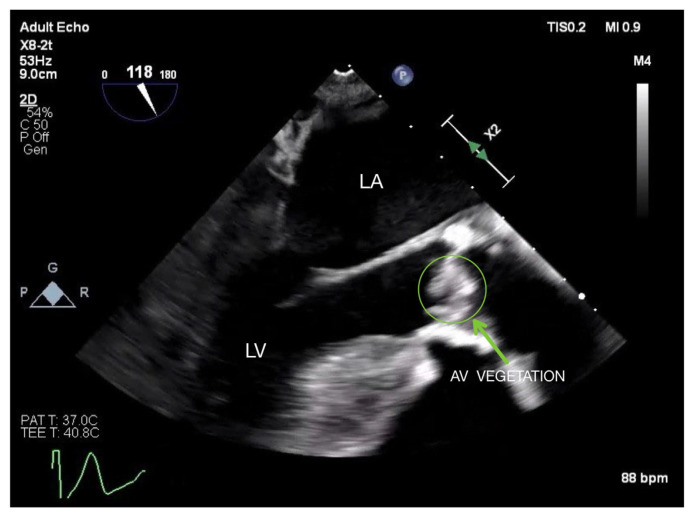

Abstract Image